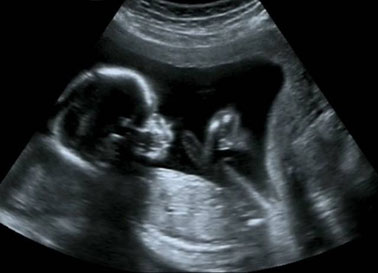

80年代-孕期B超

时间推延到80年代,中国再不用单靠手诊来感知胎儿的状态,一个个鲜活的小生命在未呱呱坠地之前就可以活灵活现地呈现在医生和妈妈们面前,这得益于一项关键技术的使用,那就是产科B超。"当时在西方国家已经被普遍使用的产科B超,一经引进中国就给中国的妇产科发展带来了极大的变革。"作为将产科B超引进中国的第一人,和睦家医疗总裁李碧菁在谈到这段历史时不禁感叹。

更加科学的产检方式让新生儿的死亡率大幅下降,中国同期的新生儿千人死亡绝对数从1950年的122降到了2010年的22。虽然很多时候公立拥挤、冰冷。但是科学的生育手段和卫生条件还是让更多的产妇顺利地成为母亲。